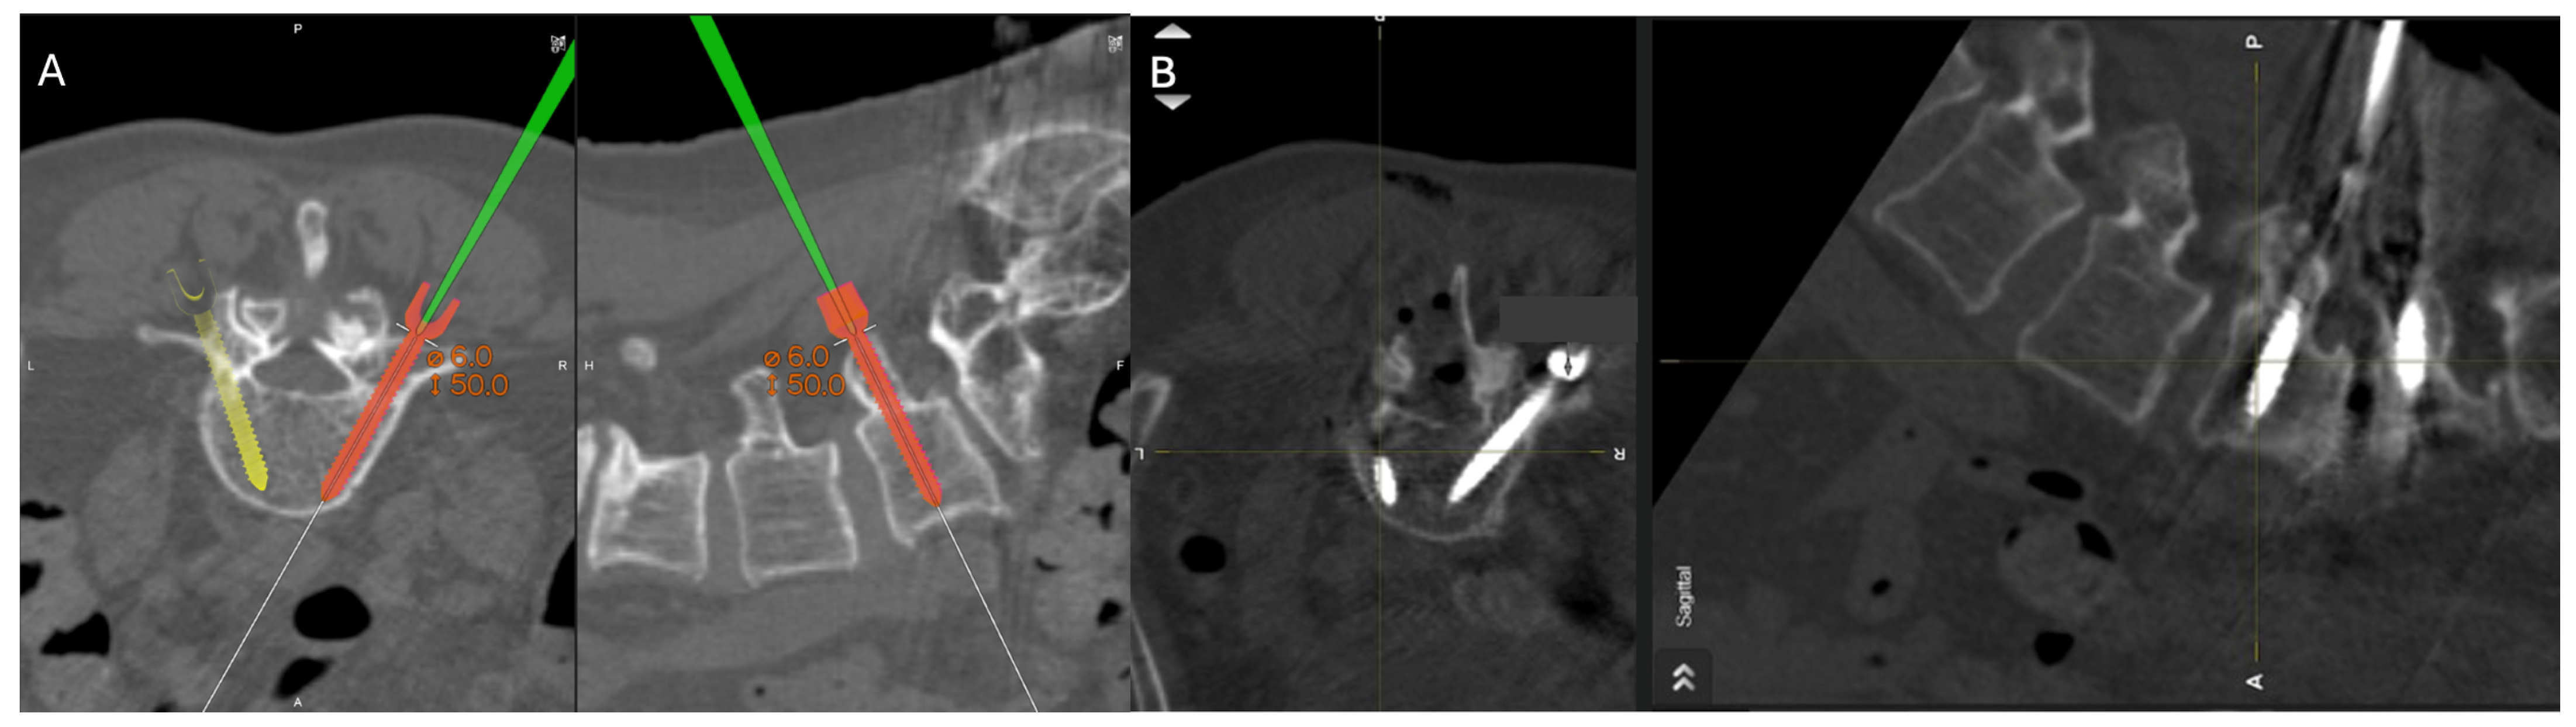

2.2. Surgical Approach

- The navigated screw with the screw driver is calibrated.

- A final intraoperative CT is completed with the navigation reference in place in case of further instrument adjustment or decompression.

3.2. Screw Placement and Accuracy